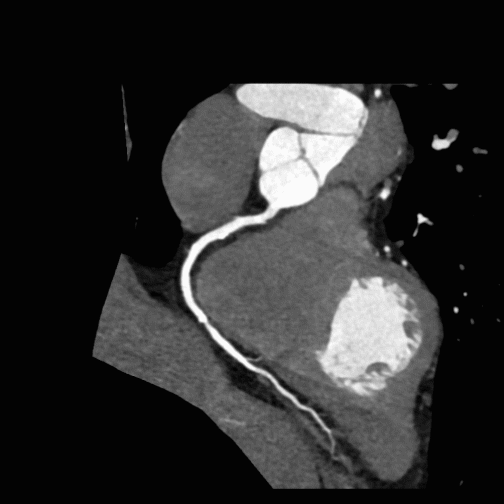

Our Heart & Coronary Angiography service utilizes CT coronary angiography to assess the heart for hemodynamically significant calcific and soft plaques, as well as any anomalous anatomy, which may be useful for diagnosing and managing cardiovascular disease. We perform Curved Planar Reformation (CPR) on areas with minimal motion artifact, ensuring the clearest possible visualization of each coronary artery.

The service includes creating detailed CPRs for the Left Anterior Descending (LAD), Left Circumflex (LCX), Right Coronary Artery (RCA), and any bypass grafts, annotating native vessel names for understanding. We further enhance our evaluations with a 360-degree loop of each CPR providing an all-encompassing view of coronary anatomy.

For optimal clarity, our segmentation process selects the cardiac phase with the least motion, focusing solely on the heart to include muscle tissue, coronary arteries, and the proximal aorta. We remove extraneous structures only as necessary, preserving the integrity of the heart model.

Our service also offers a variety of captures, including lateral and AP views of the RCA, oblique views for LAD and LCX visualization, and superior views to demonstrate vessel origins, among others. These targeted views and visual reconstructed images allow for the detailed demonstration of vessels or pathology, assisting treatment strategies and improving patient outcomes in cardiovascular care.